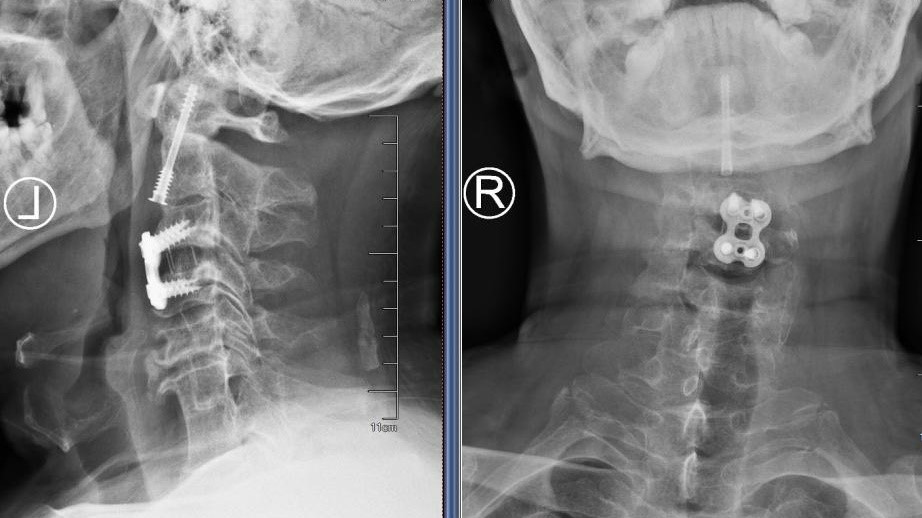

图2:术后正侧位片

在麻醉手术科的严密监护下,刘义杰副主任医师首先熟练地完成了颈椎前路C3-4减压融合术(ACDF),成功解除了脊髓的压迫。然而,通过同一个仅3厘米的微小切口,精准地将螺钉植入游离且向后倾倒的齿状突具有极大的挑战性。关键时刻,骨科手术机器人发挥了“超级助手”的作用。团队利用机器人导航系统,对进钉点和角度进行了反复测算与调整,导针精准抵达目标。随后,由姜为民主任专利研发的一枚新型齿状突螺钉顺着通道顺利旋入,牢牢锁住了骨折端。整个过程出血量少,手术顺利完成。

患者侯师傅术后苏醒后,原本瘫痪的四肢便能恢复活动。术后第一天,他的四肢肌力已恢复至4级左右;术后第二天,他便能在定制颈部支具的保护下起床进行功能锻炼。从近乎全瘫到重新站立,其间仅经过短短两天时间。患者及家属对治疗效果激动不已,表示感谢。